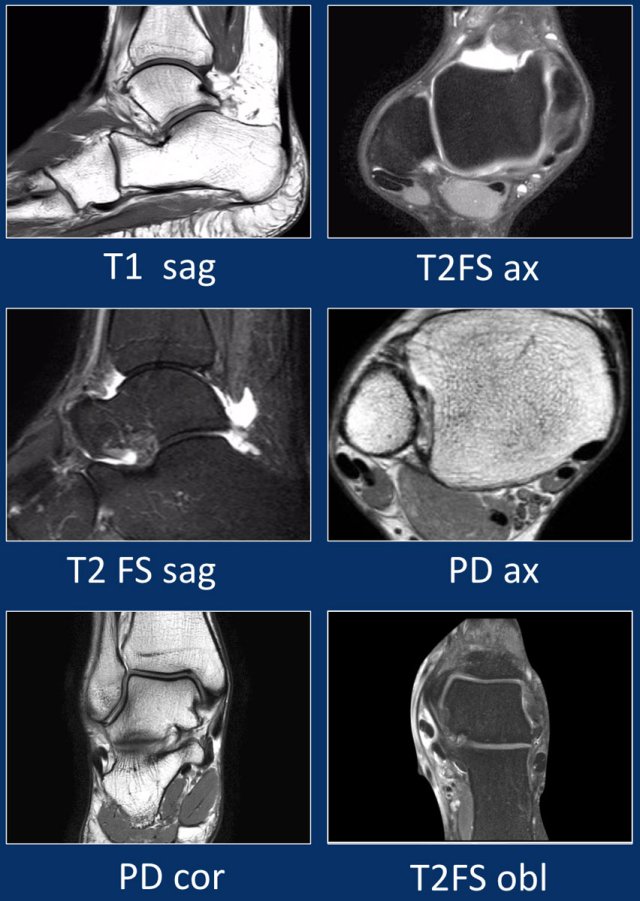

MRI protocol

Standard axial, coronal and sagittal planes are used in the ankle both on 1.5T and in 3T.

In addition to the standard planes, a oblique scan is sometimes included oriented perpendicular to the peroneus and tibialis posterior tendons.

Small tears or subtle tendinopathy are better visualized on these views.

The orientation of the tendons along the medial and lateral malleolus can cause the 'magic angle artifact' to occur.

The tendons will show relatively hyperintense signal at 55* to B0), simulating pathology like tendinopathy or partial tears.

This artifact is visible on short TE images (f.e. PD).

On long TE images (like T2) this artifact does also occur but less pronounced.